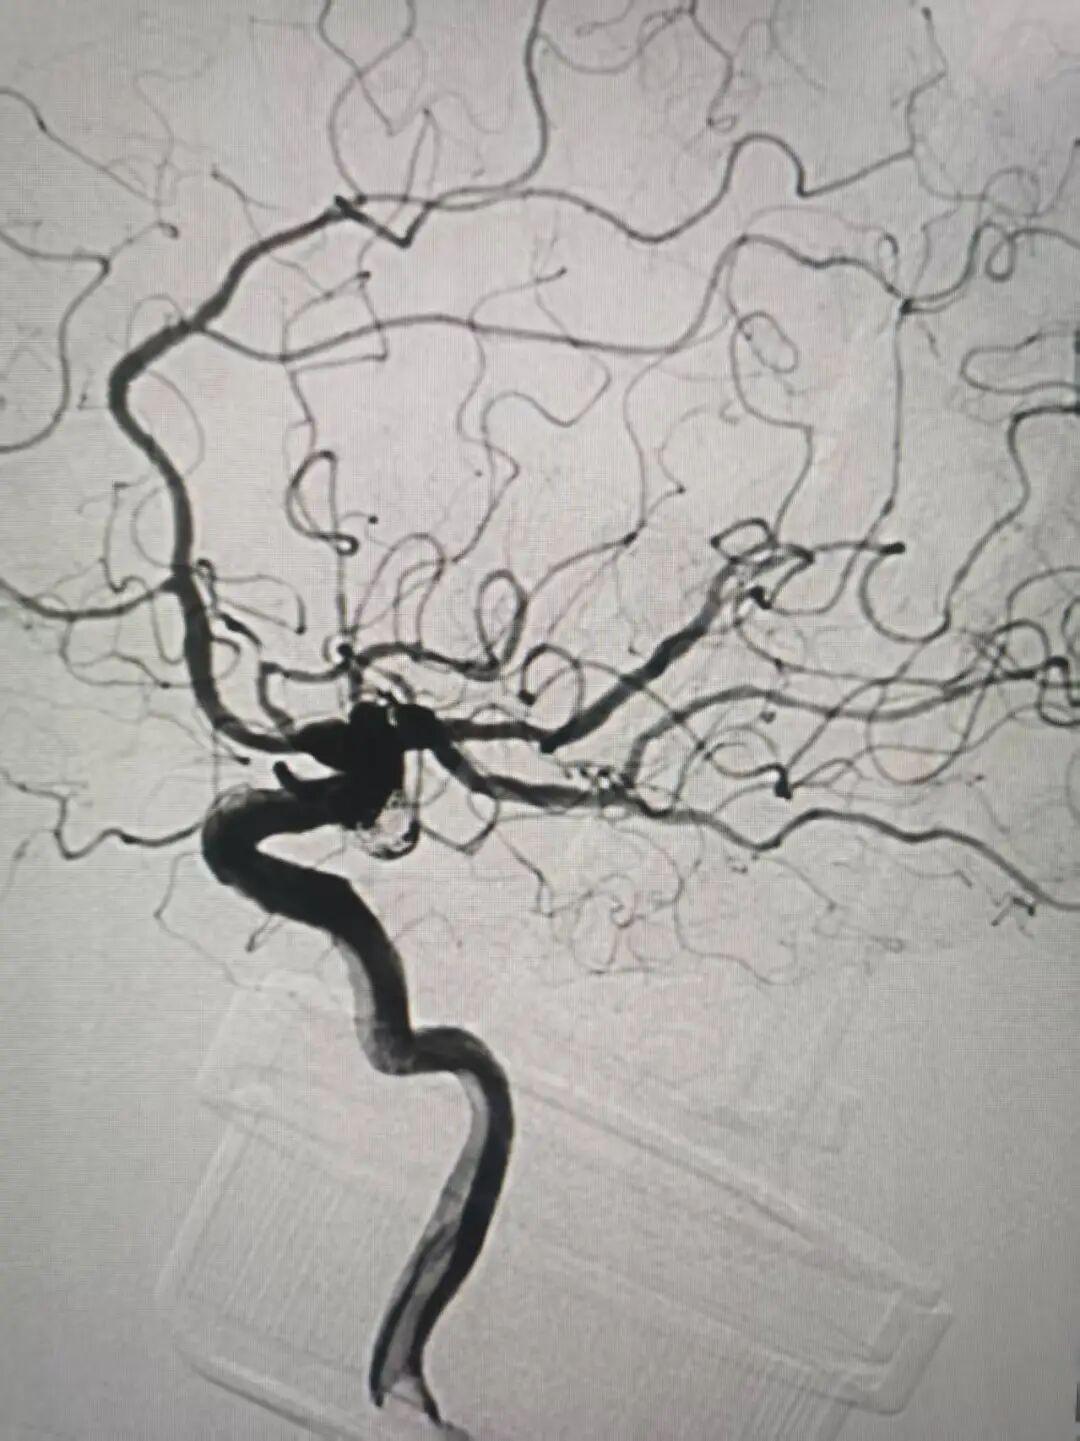

通道建立,保护到位。随后,一枚枚柔软的弹簧圈被精准填入动脉瘤腔内,致密填塞,彻底消除了破裂风险。最终造影显示:动脉瘤被完全栓塞,不再显影;而左侧大脑后动脉血流通畅,无任何狭窄或闭塞,手术取得圆满成功!

术后,患者恢复良好,头痛症状消失,神经功能完好无损。此次为80岁高龄患者实施高难度动脉瘤介入手术,面对复杂解剖结构与多重手术风险,团队凭借“神龙摆尾”等前沿微创技术精准攻坚、圆满成功,填补了医院在高龄复杂脑动脉瘤微创介入治疗领域技术的空白,实现脑血管疾病微创诊疗关键突破。外二科主任表示,随着人口老龄化,高龄脑血管疾病患者日益增多。本例手术充分证明,医院已具备在高龄、复杂解剖条件下开展危重脑血管介入治疗的成熟能力,以技术突破筑牢高龄患者生命防线,大幅提升区域脑血管疾病救治水平。